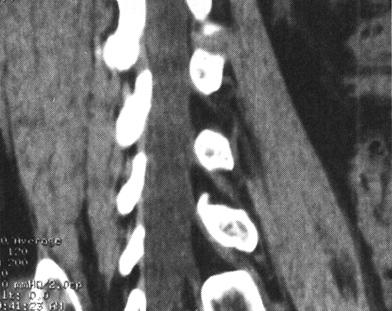

CT在脊柱脊髓损伤中应用很广泛,横断面成像是诊断脊椎骨结构创伤的主要手段,它可显示X线平片不易显示的细微骨折和小关节脱位,并能够很好地显示骨性椎管的情况,可为评价脊髓受压情况提供重要的影像学信息。螺旋CT扫描技术可对患者进行快速连续多部位成像,并支持多平面及三维成像。因而CT扫描对理解脊柱复杂解剖部位,发现细微病变有十分重要的临床意义(图7-4至图7-6)。甚至明显侧弯变形脊柱的冠状面重建亦可通过严格按照脊柱弯曲度改进的软件而获得。单纯轴位扫描很容易漏诊与CT断层面平行的骨折,例如,发生在齿突基部和胸腰水平的创伤,在横断位扫描中不能显示横断水平的骨折线,但在高质量的冠状、矢状和三维的重建图像中显示良好(图7-7至图7-10)。

图7-7、图7-8 多排螺旋CT2D重建,显示C2齿状突基底部骨折

图7-9、图7-10 多排螺旋CT3D重建,显示骨折线走行及累及骨表面